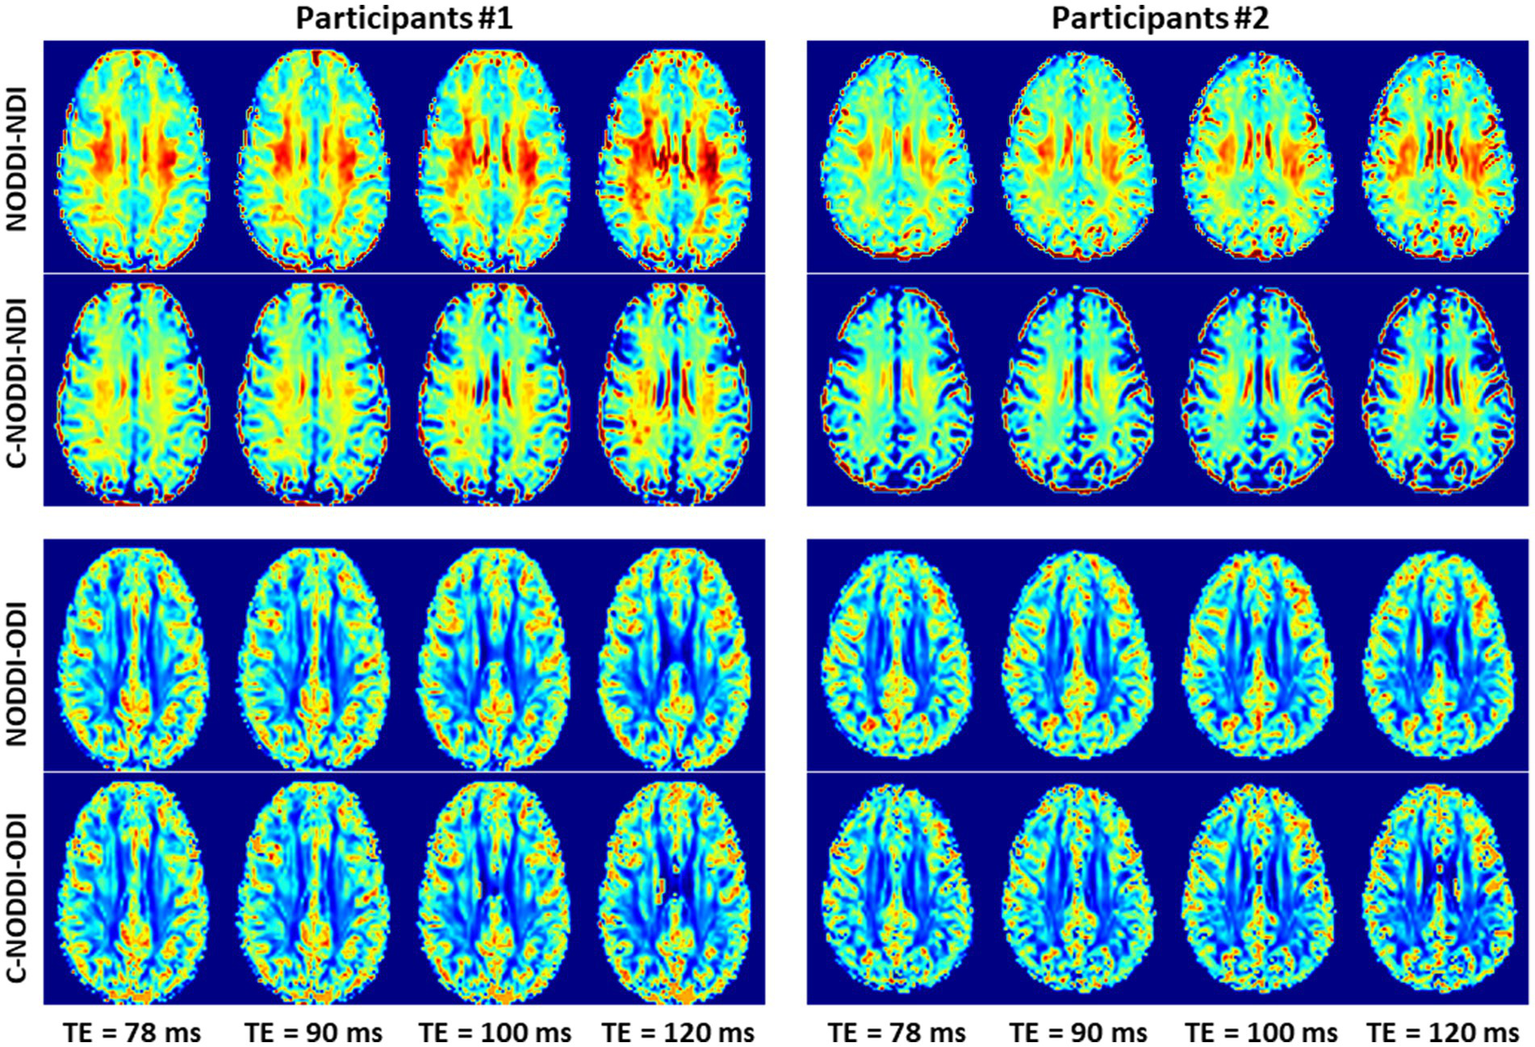

Finally, Figures 89 show, respectively, examples of derived NDI and ODI maps and mean parameter values calculated over the whole WM region using NODDI or C-NODDI at several TEs using DWI data acquired from the brains of two participants. Visual inspection and quantitative analysis indicate that derived NDI estimates using NODDI are TE-dependent exhibiting increased values with TE increases. In contrast, the NDI maps and mean values calculated using C-NODDI exhibit lower dependence on TE. However, although the majority of the white matter regions exhibited relatively lower dependence on TE, some regions showed substantially increased values with TE. Further, it is readily seen that the ODI maps calculated using NODDI or C-NODDI are similar and with mean values virtually constant as a function of TE. Moreover, we note that derived NDI and ODI maps exhibit some regional differences across TEs; this is due to differences in signal-to-noise ratio due to differences in TEs leading to signal drops at higher TEs, as well as to some persisting image misregistration.

Figure 8

NDI and ODI maps derived using NODDI or C-NODDI from DWI data acquired at different TEs from the brains of two different participants. Results are shown for a representative slice for each of the participants.